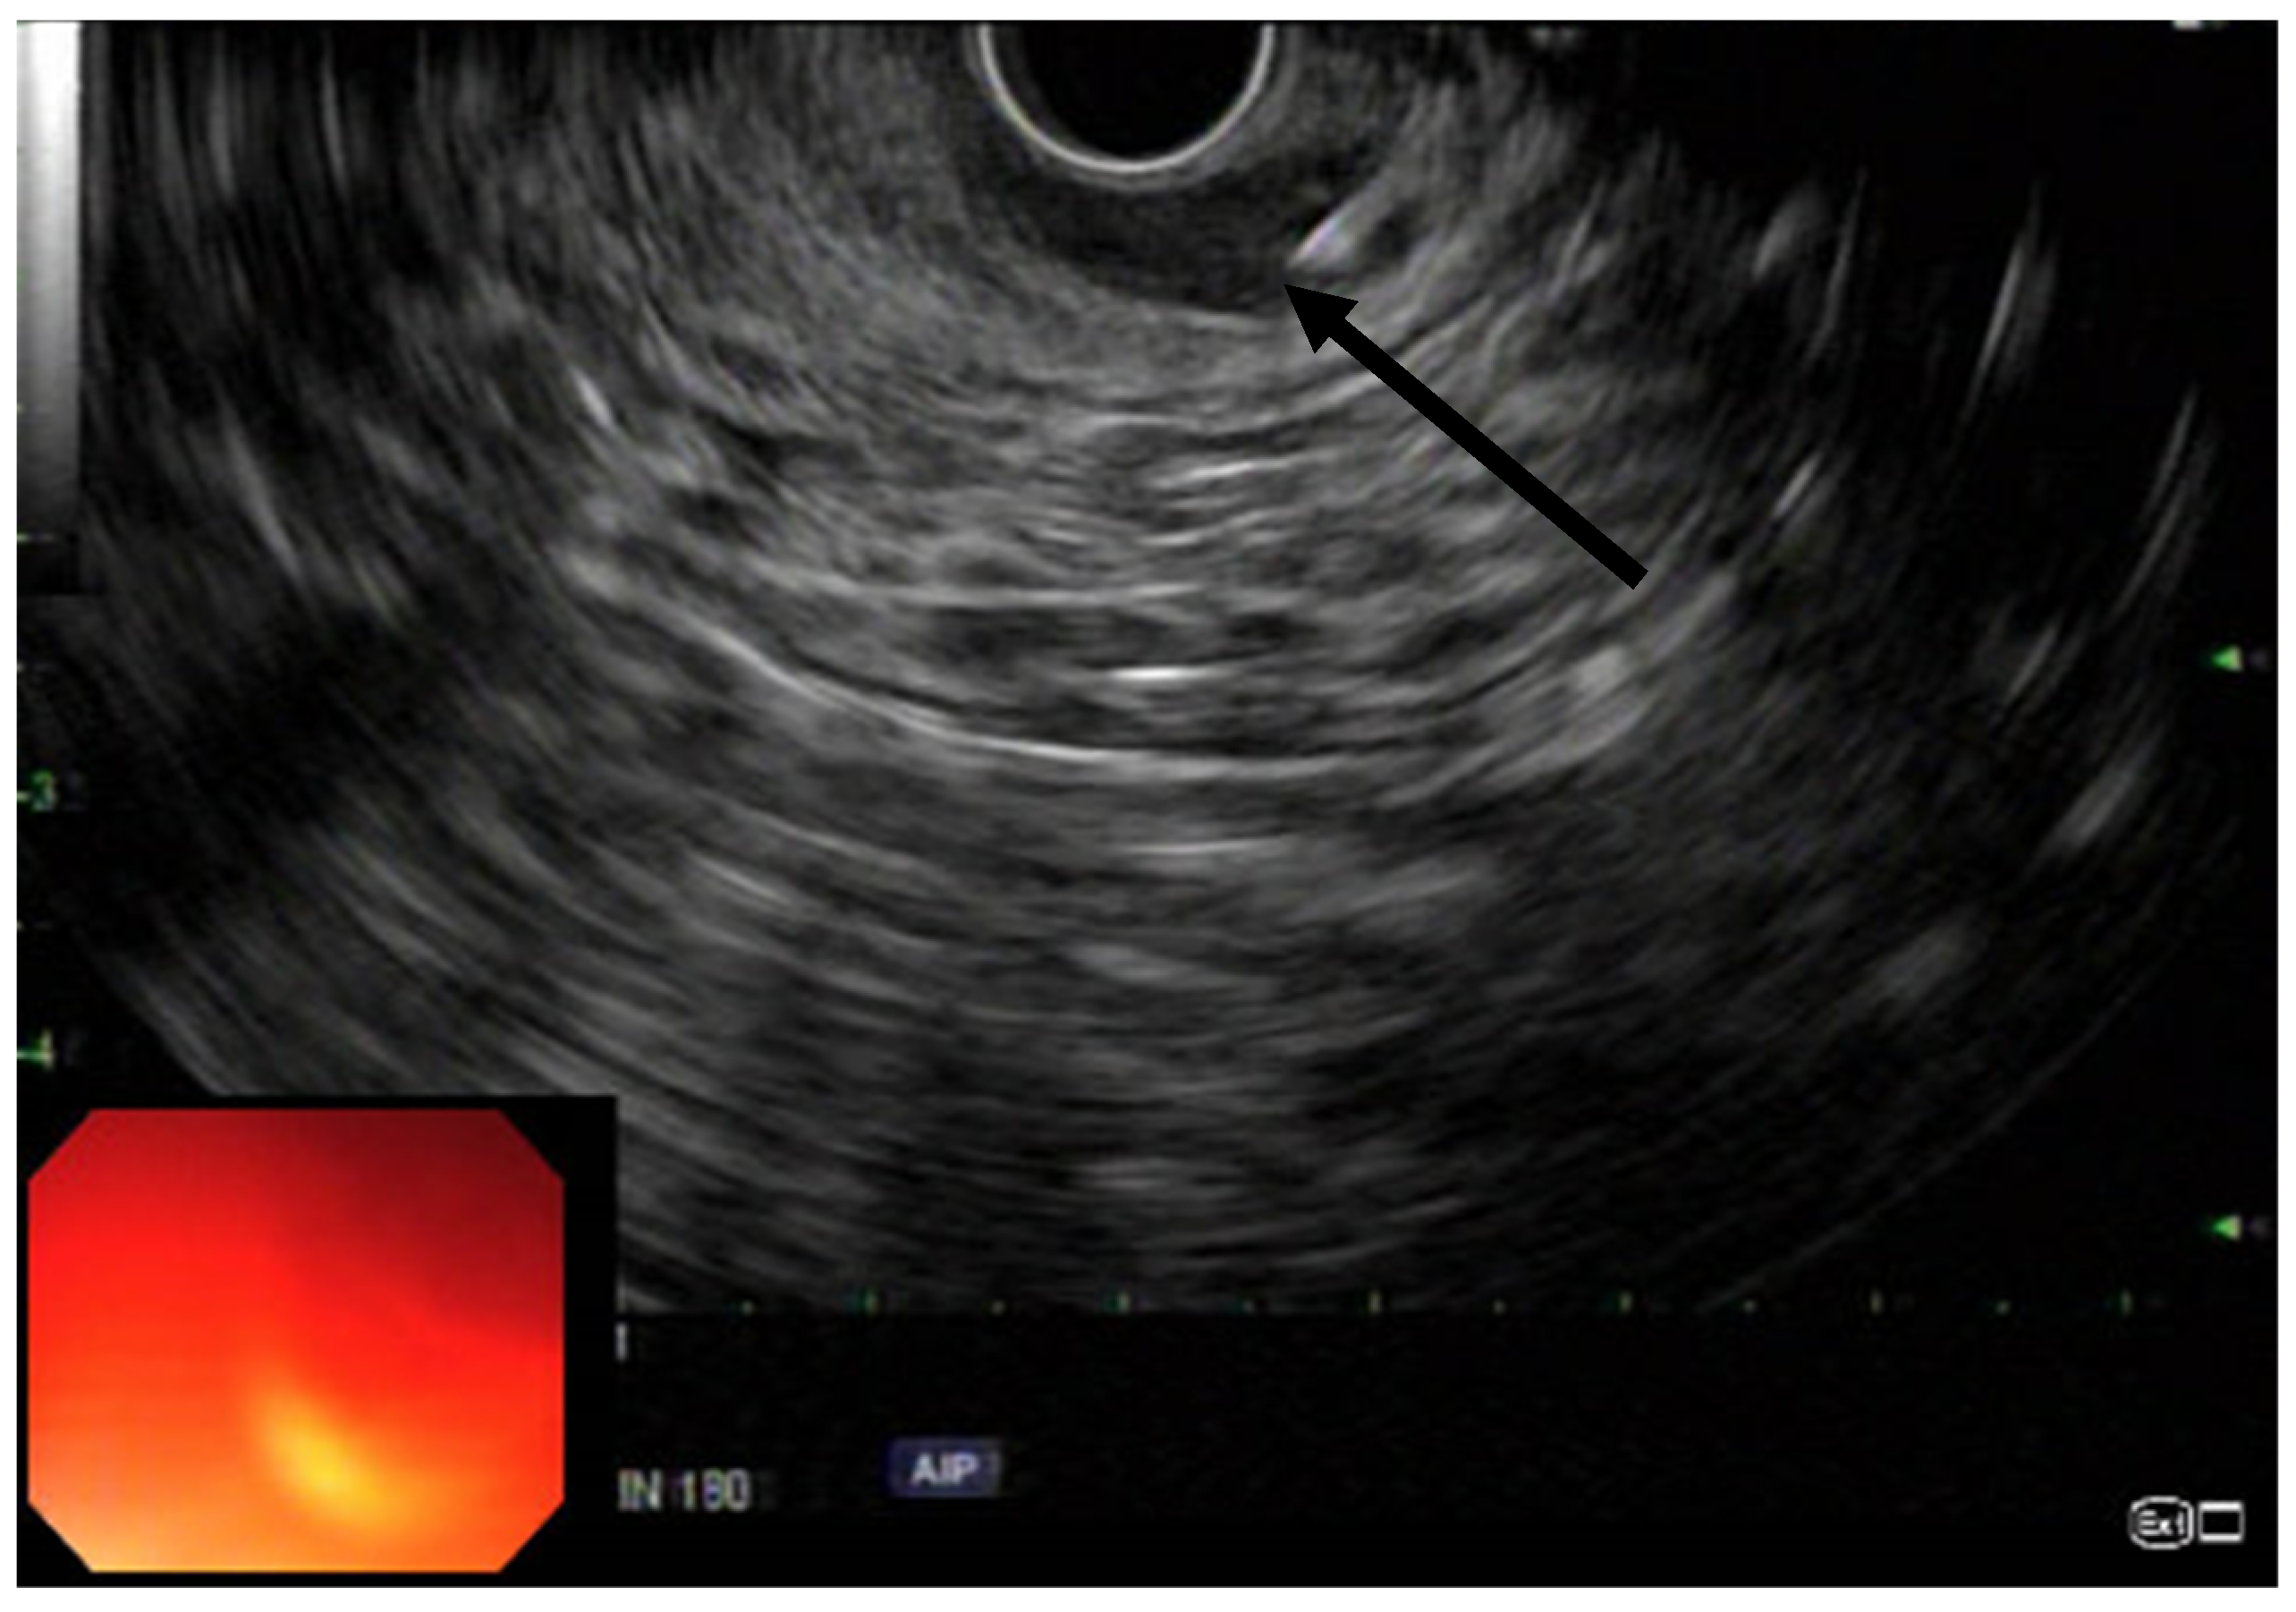

EUS was performed using a linear array echoendoscope (Figure 1, Figure 2 and Figure 3). Eighty units of type A botulinum neurotoxin was diluted in 2 cc of isotonic saline. An echoendoscope was introduced into the anal canal. The internal sphincter was identified sonographically and a 25-gauge needle was introduced into the internal sphincter. Then, 0.5 cc of saline-containing 20IU BTX was injected into the internal sphincter. The needle was withdrawn, the scope was rotated 90 degrees and the second injection was given. This process was repeated for a total of 4 times giving 0.5 cc per quadrant. Conscious sedation or MAC anesthesia was used for the procedure.

Figure 3. Linear EUS with arrow pointing to the needle injecting the IAS with expansion of the IAS due to the injection.